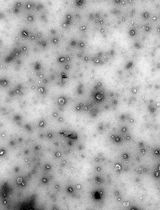

Dynamic light scattering analysis showed that the average sizes for blank nLNPs (Figure 3) and IL-22/nLNPs (Figure 5) are 189.9 ± 69.3 and 184.2 ± 84.96 nm, respectively, based on triplicate measurement.

Figure 3. Measurement of size in blank nLNPs. Particle size was determined to be 189.9 ± 69.3 nm in diameter.

Figure 5. Measurement of size in IL-22/nLNPs. Particle size of IL-22/nLNPs was 184.2 ± 84.96 nm in diameter.